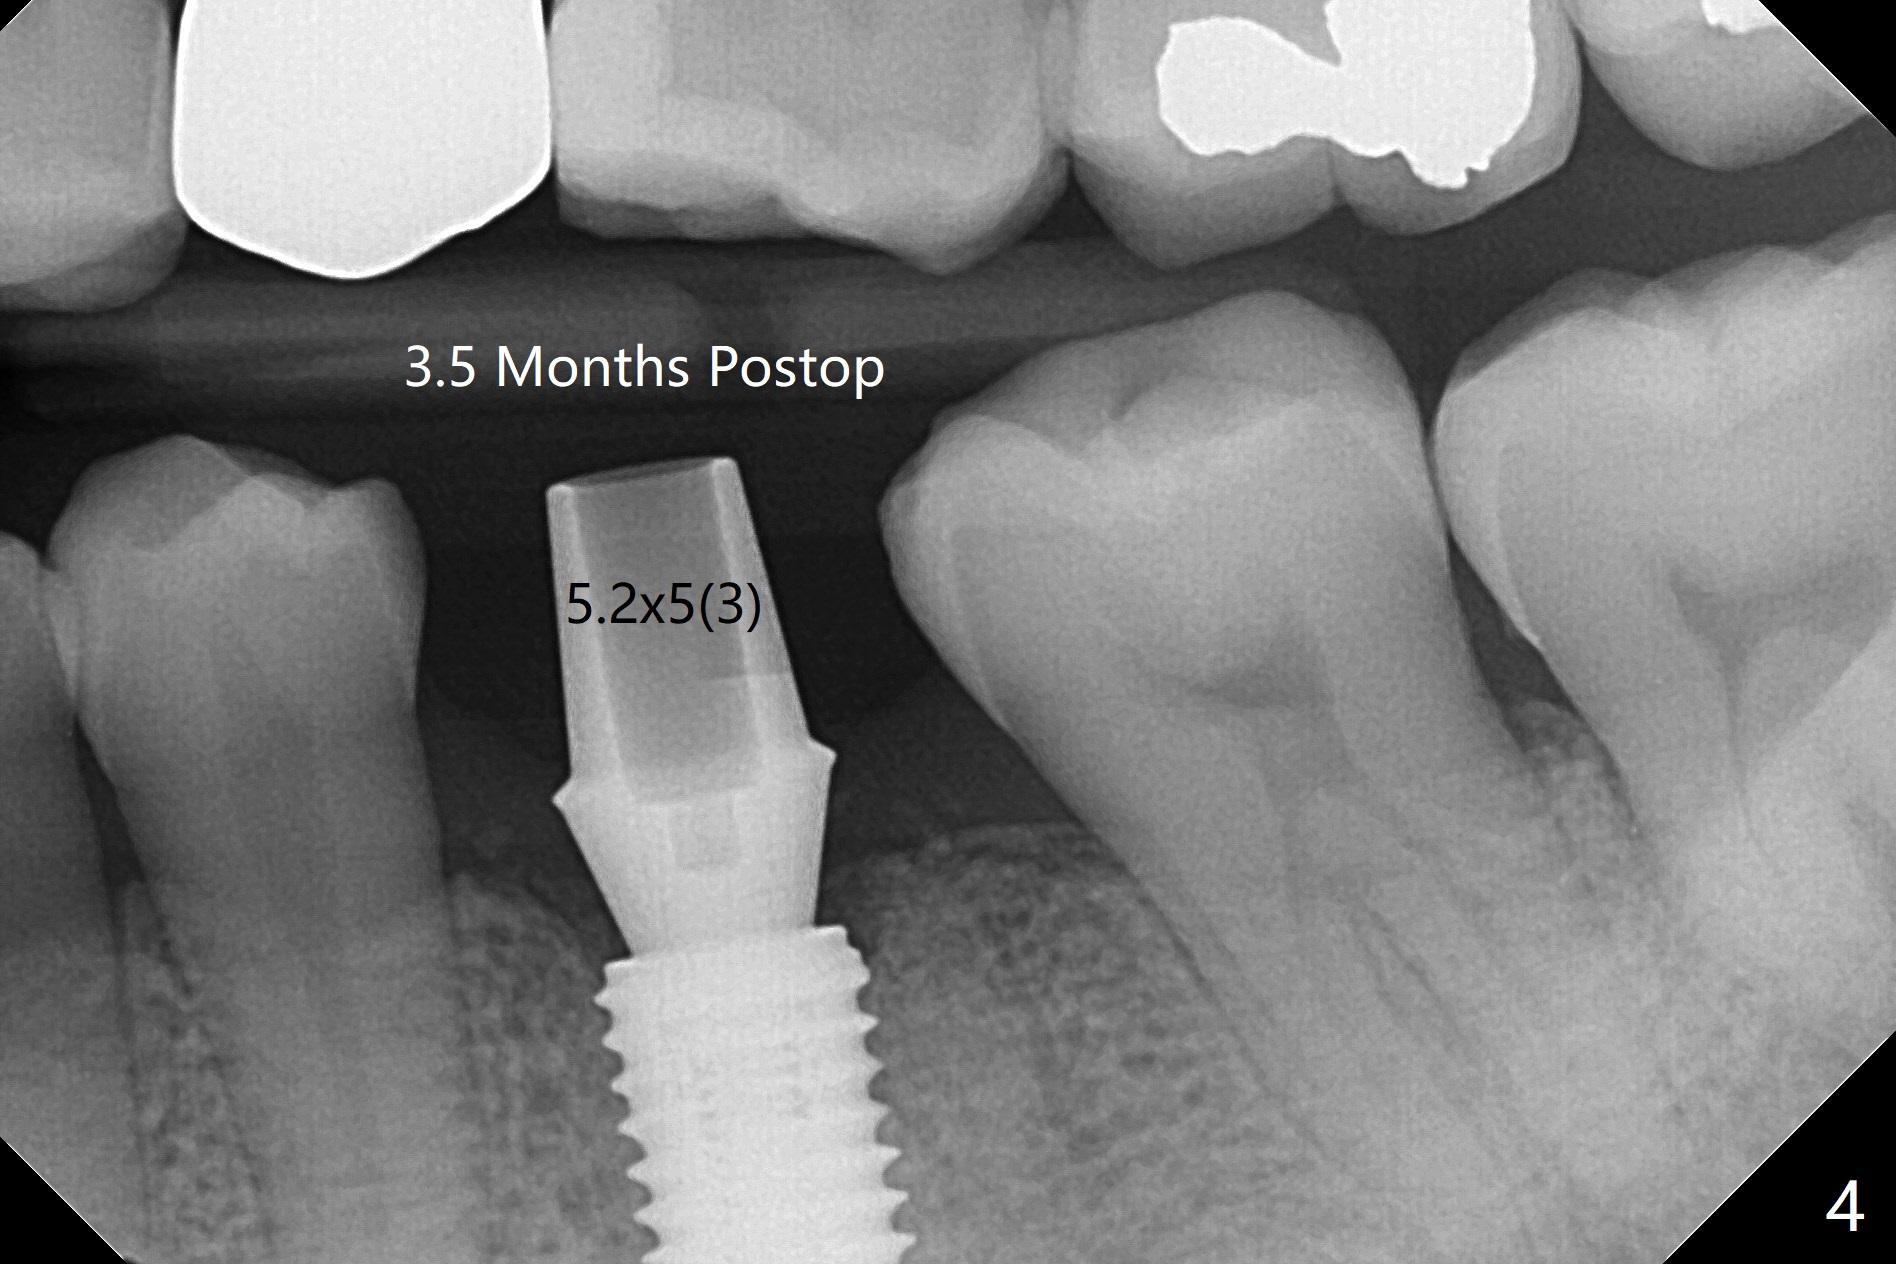

50来岁男,左下6位点保存术后4.5个月回来做导板植牙术,牙槽嵴和角化龈宽,几乎是最理想的手术。唯一担忧的是牙槽骨够不够硬(植骨后4.5个月),其实为了植入5毫米植体(图一),最后钻头必须4.5毫米,而且需要使用4.5毫米皮质骨功螺纹钻头,反复多次倒旋植体,最后扭力50Ncm,唯恐造成骨坏死。使用6毫米profile钻头后,放置6x4毫米基台,后者完全就位(图二,三)。术后病人汇报他根本感觉不到做过植牙术,以前做过徒手即刻植牙(30 13)。术后3.5月去除愈合基台,牙龈袖健康,使用Prosthetic treatment planning基台(没有六角形,容易就位,选择袖高度),放置修复基台(图四),拧紧20Ncm(厂家推荐30Ncm),放置plumber tape and Cavit,取模。口内粘固,事先牙冠(带有access hole)边缘涂凡士林,容易去除残余粘固剂,争取不取出基台,减少牙龈附着破坏。